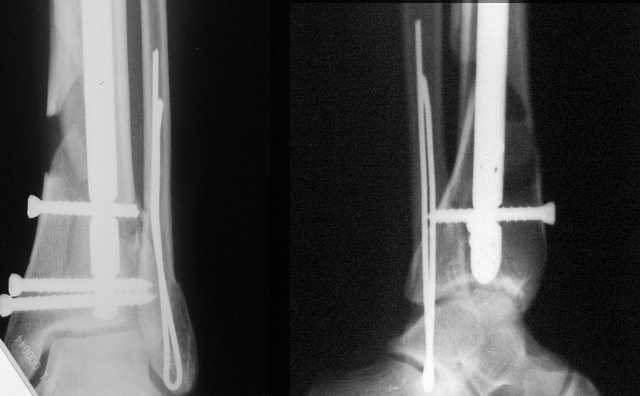

Да и нет! Зависит от перелома и способа остеосинтеза. А результат? (01)

Кликните для загрузки файла 01.jpg

65KB (66785 bytes)

Мы же говорили о проксимальном плече. При переломе tibia, конечно, речи о двух Y-спицах нет. Еще раз о них - пружинящая подвижность без "срезающих" перемещений фрагментов - дополнительный стимул к образованию периостальной мозоли.

А в данном случае - у нас был бы применен locked nail с еще меньшими дырочками на коже и с возможностью полной нагрузки немедленно после операции. Какие тут аргументы в пользу выбора пластины, а не интрамедуллярного гвоздя?

АЧ>Какие тут аргументы в пользу выбора пластины, а не интрамедуллярного гвоздя?

Классически показанием для locked nail яв-ся зоны BC CD, до появления LCP показания к locked nail несколько расширялись в зоны AB и DE

Аргументы: перелом достаточно низкий, трудно будет ввести 3-и блок. винта, а учитывая характер перелома на 2-х дистальных винтах я бы не рекомендовал немедленную полную нагрузку.